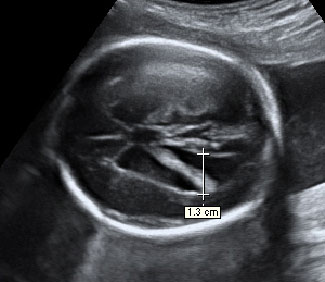

En la imagen ecográfica podemos ver el corte de la cabeza fetal donde se muestra la medición de un ventrículo cerebral aumentado de tamaño (o ventriculomegalia).